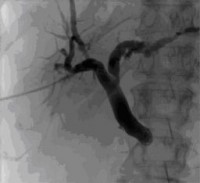

Externe Gallenwegsdrainage (PTCD) bei Gallenabflussstoerung infolge eines Pankreaskopftumors.

Percutaneous transhepatic cholangiography (PTCD) is a procedure in which bile is drained from the liver to the outside into a bag. It is used in cases of dilatation of the bile ducts (cholestasis) that cannot be drained into the intestine by ERCP (endoscopic retrograde cholangiopancreatography) for technical reasons (tumor that cannot be passed, Z.n. surgery).

Figure: External biliary drainage (PTCD) for biliary outflow obstruction due to pancreatic head tumor.